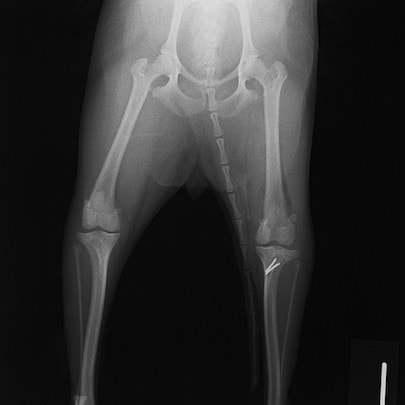

■ 症例20 ポメラニアン 8ヶ月 1.8kg

左右膝蓋骨脱臼 グレードⅢ

2ヶ月前から間欠的跛行が認められ、両膝の膝蓋骨脱臼整復術を行った。

手技は縫工筋及び内側広筋の解放、脛骨粗面の外側転位、滑車ブロック形造溝術、内外側関節包の縫縮を選択し実施した。

右側の膝蓋骨脱臼は上記手技で整復されたものの、左側はそれのみでは膝蓋骨が浮く様子が認められた。その為、PDS縫合糸にて膝蓋靱帯を1糸のみ縫合し、靱帯の縫縮を行った。

膝蓋骨脱臼は膝関節における膝蓋骨の内外側の脱臼と定義されるが、時として単純な内外の脱臼ではなく、膝蓋骨が大きく前方に浮き上がるように脱臼する場合がある。特にトイプードルやポメラニアンといった犬種に多く認められる。

内側脱臼に加えて前方への浮き上がりを矯正する為に、従来より脛骨粗面転移により膝蓋靭帯を外方と下方に引っ張り、固定する方法を選択する。膝蓋骨の前方への浮き上がりが軽度の場合は、従来法ではなく関節包の縫縮で対応していた。しかし、一部の症例で膝蓋骨の動きが悪くなり伸展機構が円滑に機能せずロボット様歩行になるケースがあった。

その為、膝蓋靭帯自体を縫縮する方法を採用した。この方法により、膝関節の伸展機構を妨げず膝蓋骨の軽度の浮きを矯正することが可能となった。

本症例の経過は良好である